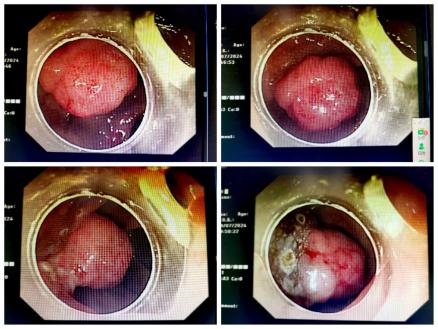

患者为老年男性,既往有“2型糖尿病”病史约15年。该患因直肠息肉行内镜粘膜下剥离术(ESD),术后病理示:管状绒毛状腺瘤(IP型),局灶癌变呈粘液腺癌。针对该病例科室进行病例讨论并制定详细周密的治疗方案。手术在麻醉科负责人赵勇实施麻醉下,由副院长张国友主刀,副主任医师郭云峰、张书法、喻祥旺共同配合下顺利完成。术后患者恢复良好。